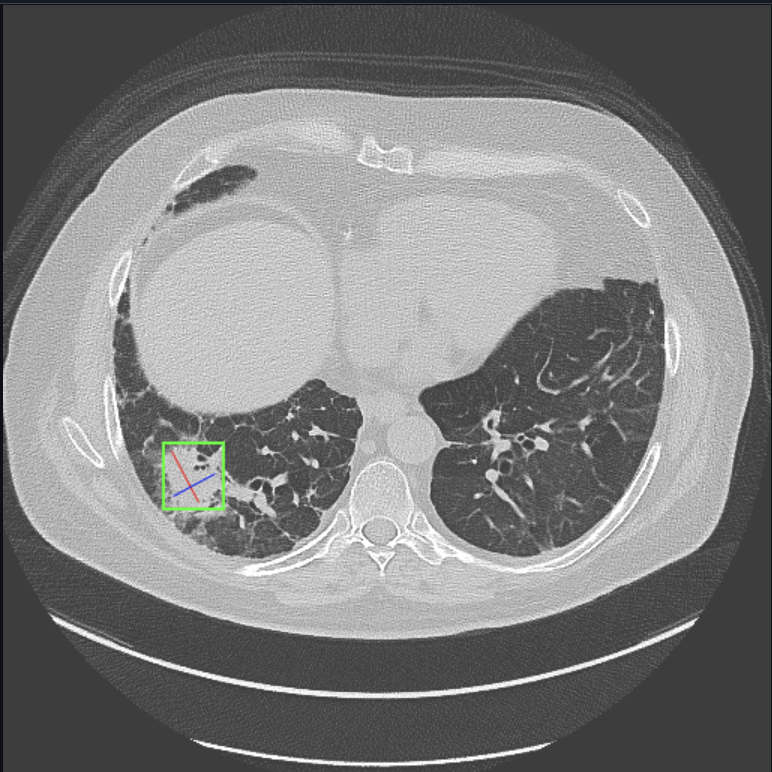

Our project uses AI to analyze X-ray scans/datasets to detect and predict lung cancer.

The project was built using the NVIDIA AI Workbench and various AI/ML libraries such as Torch and Scikit-learn. We used an extensive lung cancer dataset from Kaggle (https://www.kaggle.com/code/guslovesmath/lung-cancer-ml-classification/input) to train the Random Forest model, as well as X-ray scans of healthy lungs and those with cancerous growths to train our deep learning model.

Throughout this project, we learned the intricacies of medical image analysis, particularly when dealing with x-ray scans. We gained a deeper understanding of how to preprocess image data, handle large datasets, and apply machine learning techniques such as convolutional neural networks (CNNs) for image classification. Additionally, we became more familiar with medical imaging datasets and the ethical concerns of using sensitive health data in AI applications. Moreover, we learned the importance of teamwork. By putting our heads together, we were able to boost progress and receive instant feedback for our ideas from one another. Debugging became easier as well as three heads were more likely to spot the error than one person would. Work also turned out to be more fun as we would spend countless hours working together while socializing.